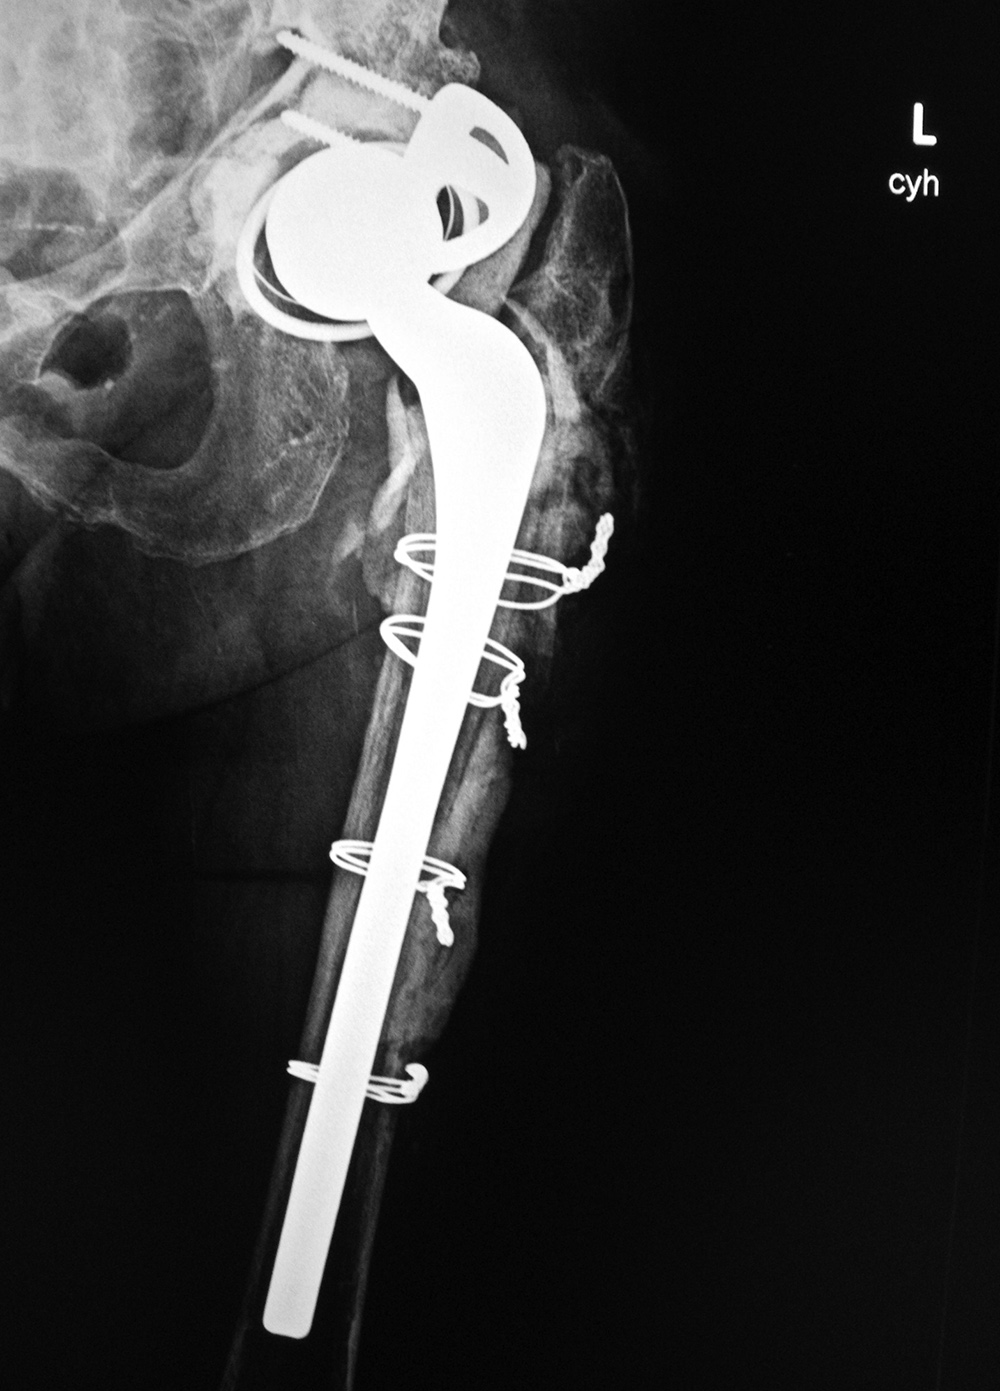

Triflange acetabular component total hip revision arthroplasty with long femoral stem |

Triflange acetabular component total hip revision arthroplasty |

The revision prosthesis was placed because of an earlier periprosthetic fracture. There are two cable wires proximally and two cerclage wires distally. |

83 year-old woman |